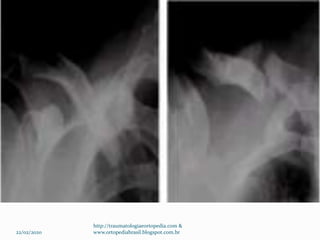

Exames Radiográficos

 Rx de clavícula AP

 Radiografia apical Oblíqua

 TC  Terço proximal – raro –

 Terço distal – Rx com estresse (4,5 Kg) para avaliação

dos ligamentos